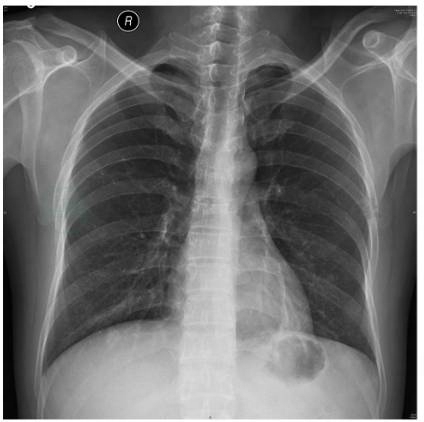

患者男性,41岁,2018年7月19日因“前胸皮疹、发热伴咳嗽、咳痰1个月余”入院。患者2018年6月15日无明显诱因双手指尖及前胸部出现红斑扁平丘疹,有痒感,局部皮温升高,就诊于上海同仁医院予以克霉唑乳膏外用,出疹4~5天后指尖皮疹消退,前胸部皮疹缩小至约7cm×7cm。出现皮疹1周后患者开始夜间发热,最高温度38.5℃,无寒战、大汗,无咳嗽、咳痰等,清晨体温可降至正常;发热3~4天后出现咳嗽、咳黄痰,咽痛,无咯血、呼吸困难等不适。6月22日就诊于外院,查血常规:白细胞:4.43×109/L,中性粒细胞绝对值:3.23×109/L,血红蛋白:134g/L,血小板164×109/L,CRP:5.4mg/L。予以头孢唑啉静滴,头孢克肟口服抗感染,最高体温未下降。6月27日再次复诊,查白细胞:5.69×109/L,中性粒细胞绝对值:4.21×109/L,血红蛋白:126g/L,血小板134×109/L,CRP:16.27mg/L。予以头孢曲松抗感染,未见好转。遂7月5日就诊于华山医院急诊,查胸片示:左下肺结节,乳头影可能(图1)。

图1 胸部正位片(2018-07-05):两肺纹理增多,左下肺结节,乳头影可能